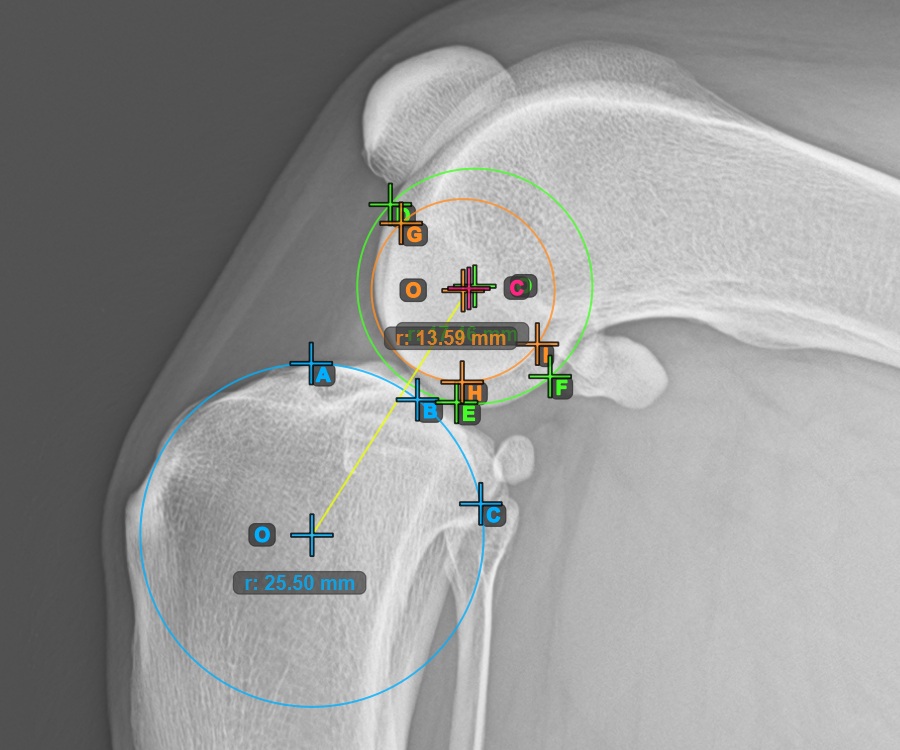

Fahren Sie fort, indem Sie die drei Punkte auf der Gelenkfläche des ersten Condylus Femoris markieren.

Markieren Sie die drei Punkte am Hauptkondylus des Oberschenkelknochens (Condylus Femoris). Unabhängig von der Reihenfolge stellen Sie sicher, dass Sie den vordersten Punkt, den hintersten Punkt und den Mittelpunkt des Condylus Femoris markieren. Basierend auf den drei gesetzten Punkten wird automatisch ein Kreis konstruiert.

Das Bild unten zeigt die typische Platzierung der drei Punkte am ersten Condylus Femoris.